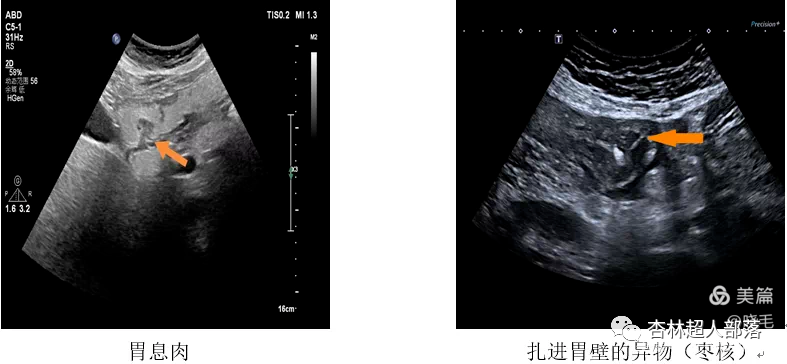

下面我们看看胃肠超声扫描出来的

这些典型病例图像吧。